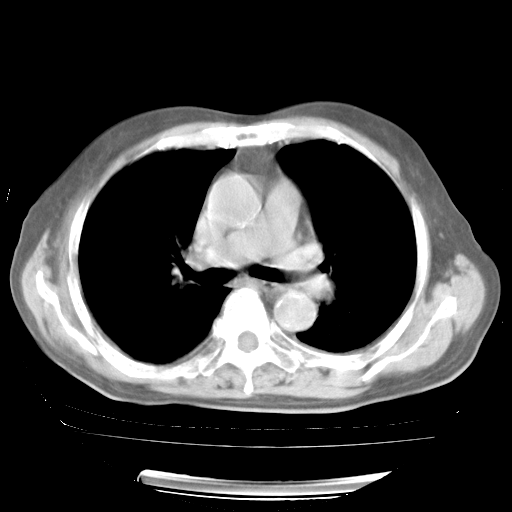

4月28日肺部CT——再次出现类似去年5月9日——透光度降低,“间质性”改变。